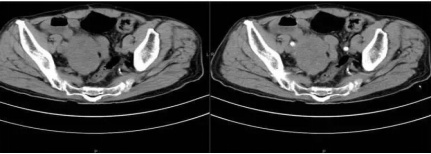

患者腹部CT提示盆腔肿瘤

由于症状不明显又缺乏特异性,胃肠道间质瘤往往难以在早期发现,尤其是直径小于两厘米的肿瘤,可能没有任何症状。胃肠间质瘤就像一个“潜伏者”躲在暗处。患者常见的早期表现主要是消化道出血、腹痛、腹块、贫血,部分患者可能会出现肠梗阻症状。许多患者都是在肿瘤普查、体检或其他手术时无意中发现患了此病。像林女士长了这么巨大胃肠间质瘤却一直没有发现,在临床上也是比较罕见的且极易被误诊为妇科肿瘤等。

鉴于间质瘤的特点,通常认为其良恶性常常与病变大小密切相关。一般直径小于2cm的间质瘤称为小间质瘤,大多数微小间质瘤表现为良性肿瘤特性,生长非常缓慢,不会引起不适也不会危及健康,不需要特别治疗,每6个月复查一次即可。然而,大于2cm的间质瘤却会随着体积的增大,表现为恶性肿瘤的特性,部分可发生恶变并转移。在临床上首次就诊的胃肠间质瘤患者中,有50%以上的患者已发生肝转移和腹腔转移,严重影响患者健康,甚至危及生命,像林女士这种大于10cm直径就已经算是高度风险了。